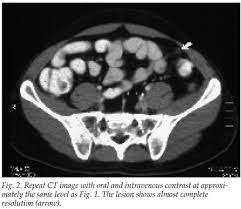

Epiploic Appendagitis